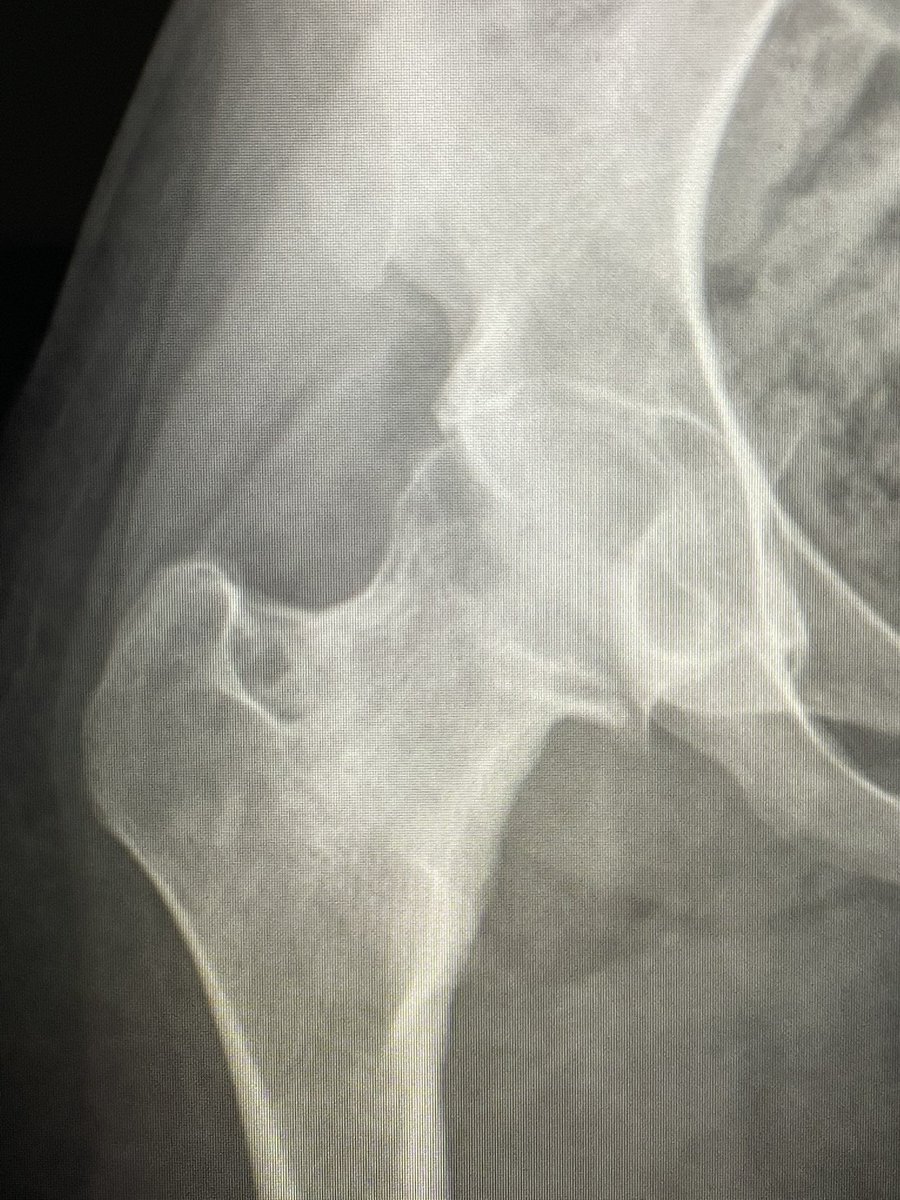

I had an opportunity to perform Intraarticular Osteoid osteoma RFA under GA

@alokmittaldr

CT confirmed it.

19 yr girl with chronic rt hip pain. One of my colleague @samrad77 diagnosed it intraarticular osteoid osteoma- rt femoral neck. I wasn’t sure.